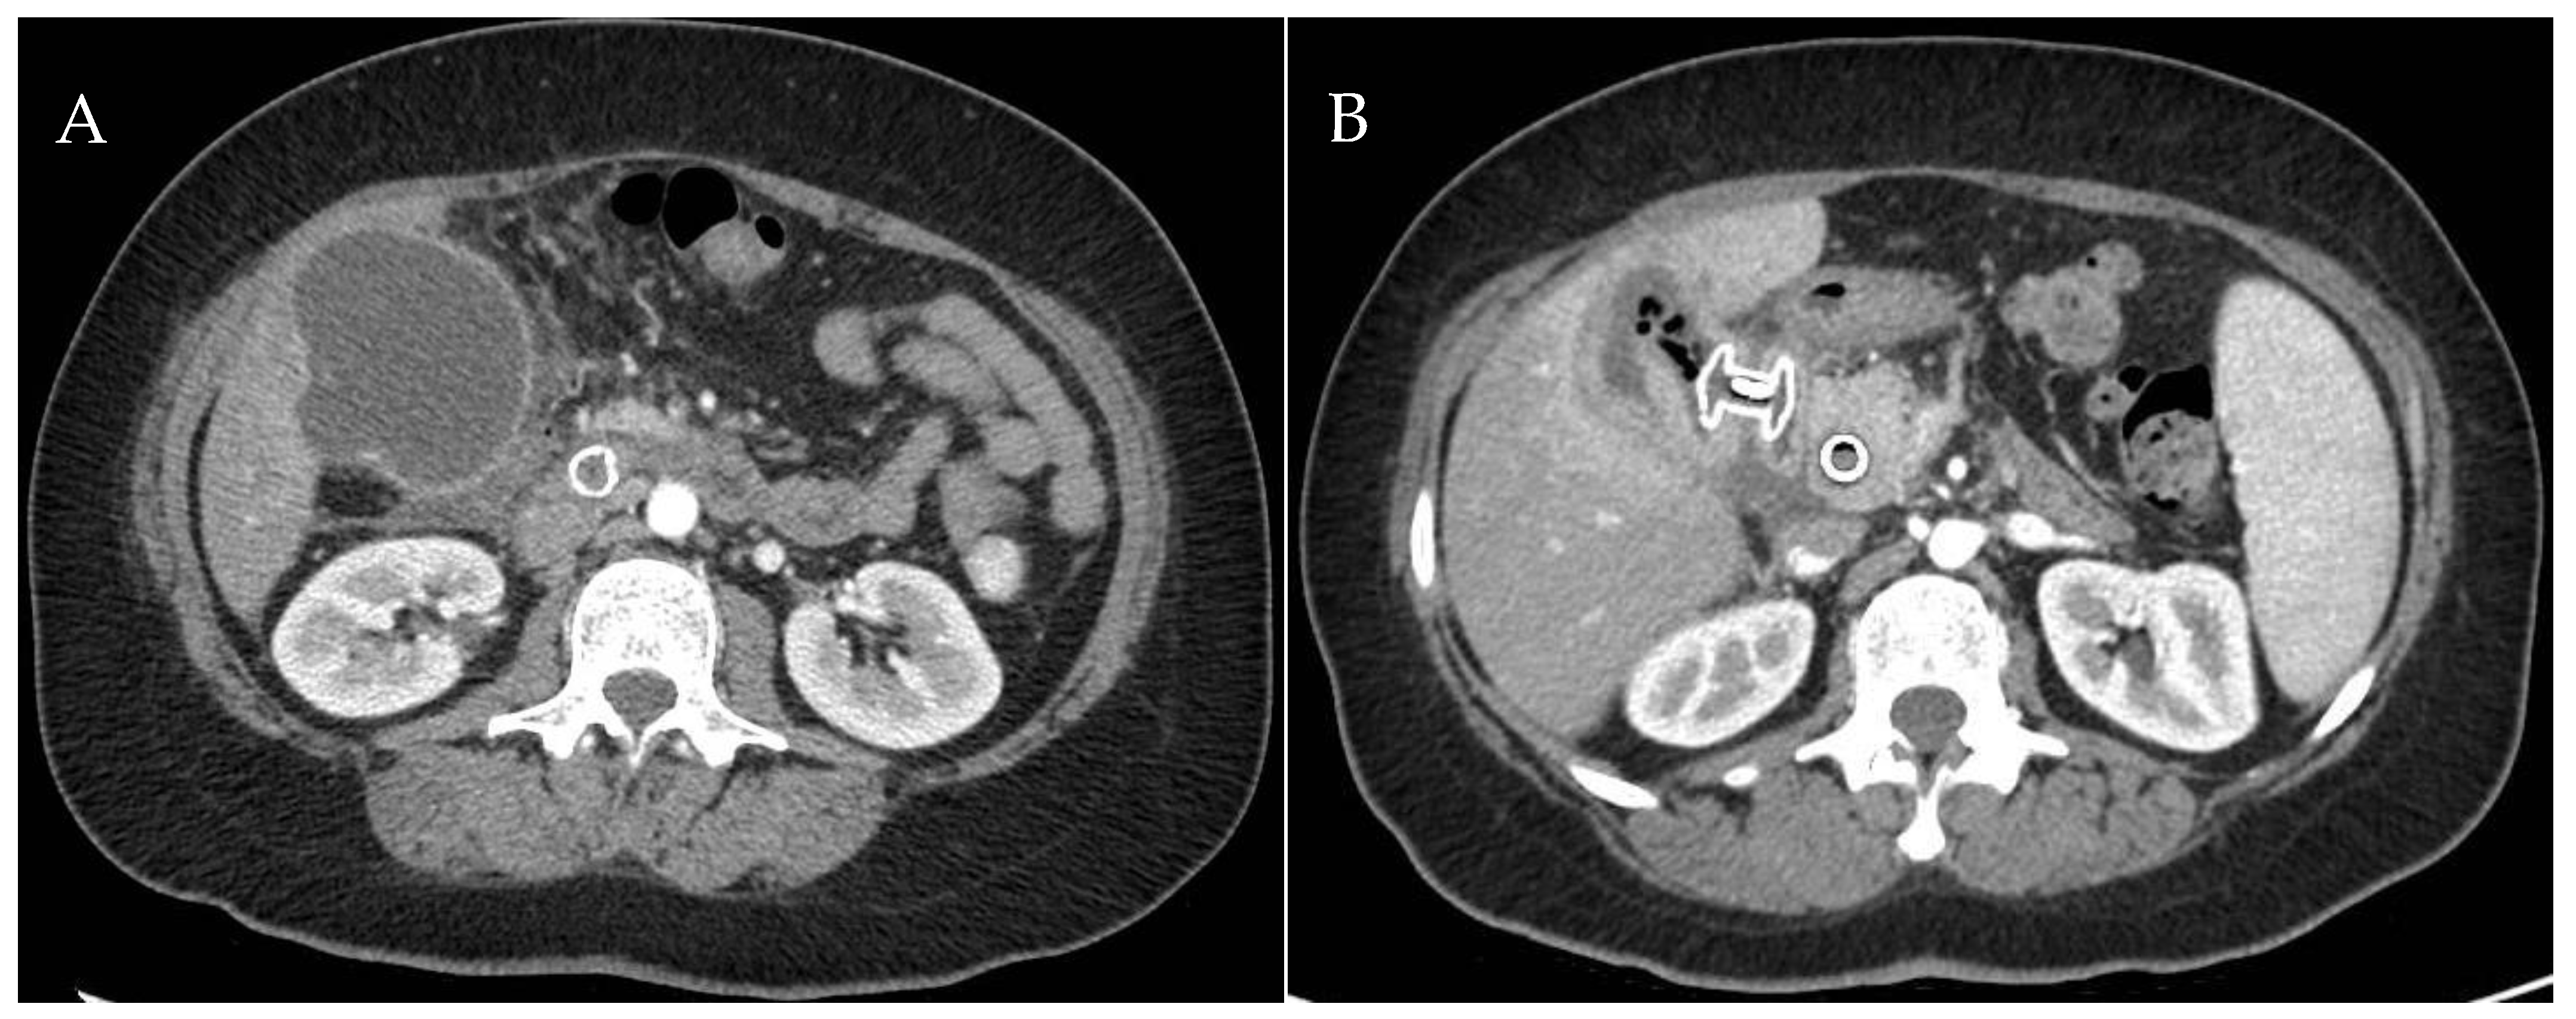

6. EUS-Guided Gallbladder Drainage in Possible Surgical Candidates

- Fugazza, A.; Khalaf, K.; Pawlak, K.M.; Spadaccini, M.; Colombo, M.; Andreozzi, M.; Giacchetto, M.; Carrara, S.; Ferrari, C.; Binda, C.; et al. Use of endoscopic ultrasound-guided gallbladder drainage as a rescue approach in cases of unsuccessful biliary drainage. World J. Gastroenterol. 2024, 30, 70–78. [Google Scholar] [CrossRef]

- Binda, C.; Anderloni, A.; Fugazza, A.; Amato, A.; de Nucci, G.; Redaelli, A.; Di Mitri, R.; Cugia, L.; Pollino, V.; Macchiarelli, R.; et al. EUS-guided gallbladder drainage using a lumen-apposing metal stent as rescue treatment for malignant distal biliary obstruction: A large multicenter experience. Gastrointest. Endosc. 2023, 98, 765–773. [Google Scholar] [CrossRef]